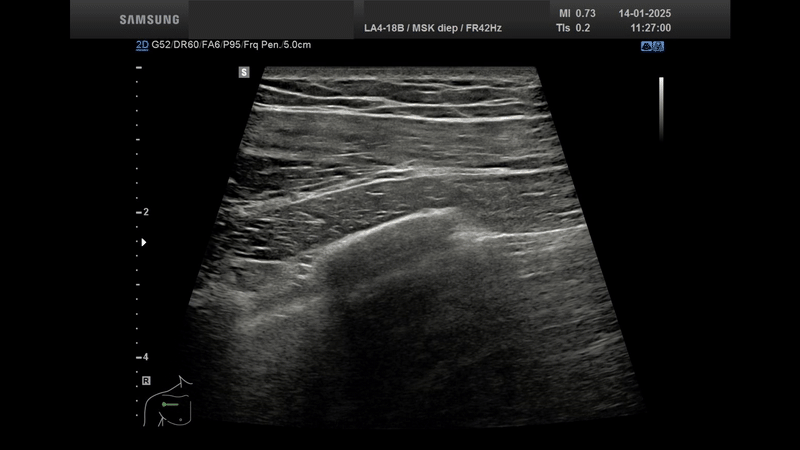

De afgelopen maanden heb ik met veel plezier verpleegkundigen van het dialysecentrum opgeleid in het gebruik van POCUS – Point Of Care UltraSound. Met behulp van een compact en mobiel echotoestel leren zij klinisch snel en doelgericht te handelen, bijvoorbeeld bij een vermoeden van overvulling of bij het beoordelen van de longen.

Module 2 behandelde de thorax en het abdomen met aandacht voor relevante pathologie.